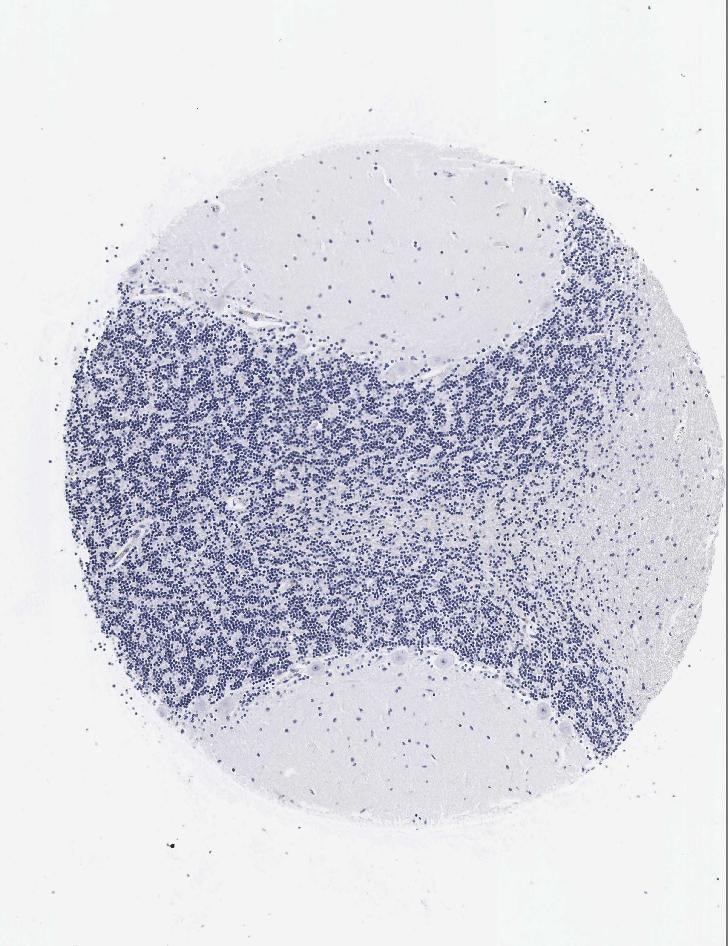

CEREBELLUM - Antibody stainingi

Antibody staining in the annotated cell types in the current human tissue is reported as not detected, low, medium, or high, based on conventional immunohistochemistry profiling in selected tissues. This score is based on the combination of the staining intensity and fraction of stained cells.

Each image is clickable and will lead to virtual microscopy that enables deeper exploration of all samples and also displays staining intensity scores, fraction scores and subcellular localization as well as patient and tissue information for each sample.

Antibody HPA001605Antibody CAB000008Antibody CAB000030

Purkinje cells Not detectedNot detectedNot detected

Cells in granular layer LowNot detectedNot detected

Cells in molecular layer LowNot detectedNot detected